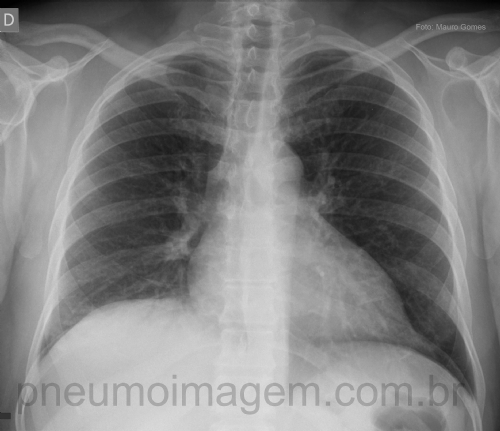

CASO CLÍNICO #8Paciente jovem, apresenta-se com tosse, febre alta (39 C) e dor torácica com início há 2 dias. Alguns raros EC na base pulmonar direita. Olhe atentamente essa radiografia de tórax e diga qual seria a sua conduta. Você trataria como pneumonia? Deixe seu comentário abaixo.

Young adult patient presents with cough, high fever (39 C) and chest pain for 2 days. Some rare crackling rales at the right lung base. Look closely at this chest x-ray and tell me what you would do. Do you would treat the case as pneumonia? Leave your comments below.